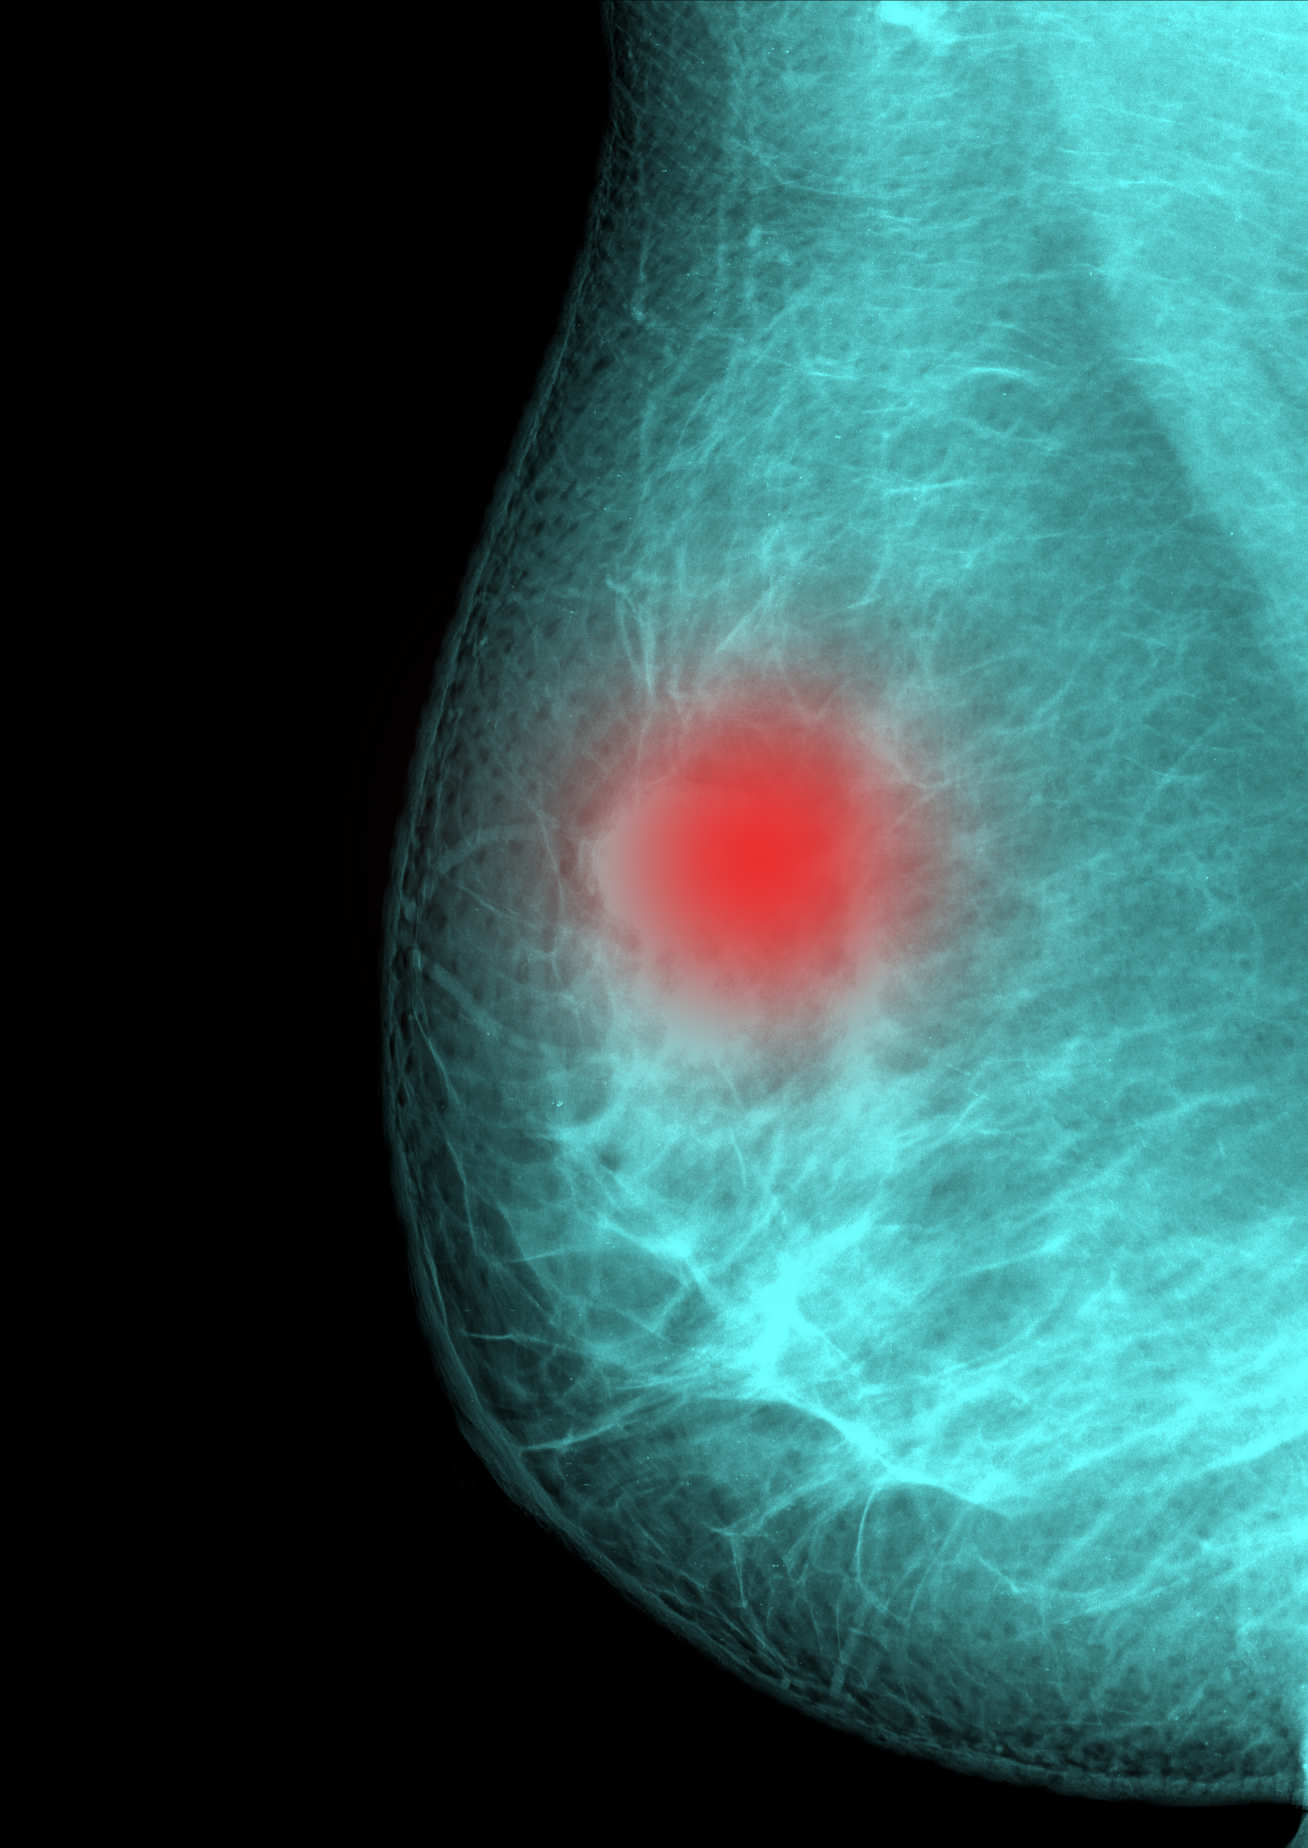

Up to one in five breast cancers are thought to be linked to faulty genes